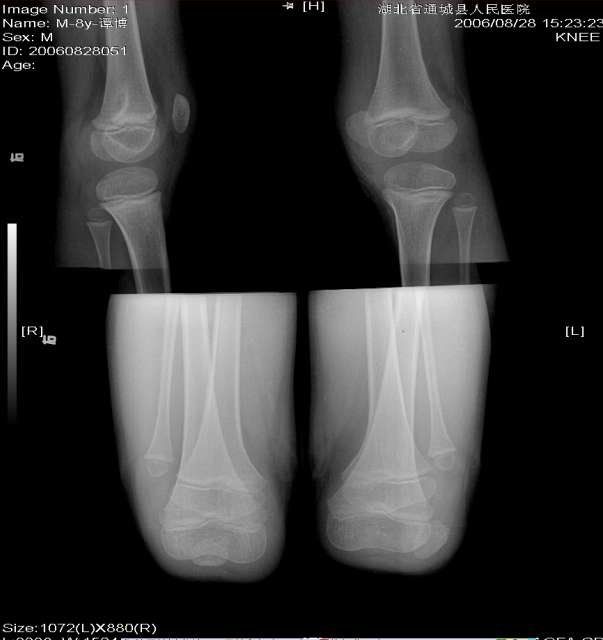

标题: PED0251:髌骨脱位 [打印本页]

男 8y 左膝

髌骨小,且向外侧移位。支持考虑先天性髌骨脱位。

支持左侧髌骨脱位。

正位片呢????脱位应该比较明确